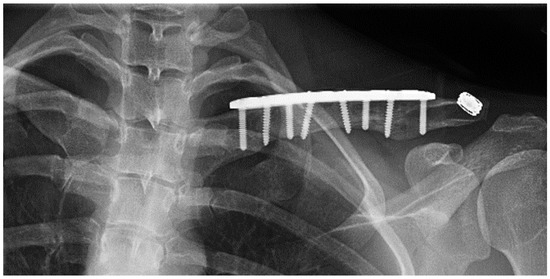

A 27 year-old female who had suffered a left clavicular fracture that was repaired previously presented with left upper extremity numbness and pain for one week. The symptoms occurred spontaneously and were intermittent throughout the week. She experienced no relief with analgesics. She presented to our Emergency Department. Brachial, ulnar and radial pulses were non-palpable. An arterial duplex revealed an occlusive thrombus of the brachial artery at the mid-humerus that appeared to be associated with the patient’s previous clavicular repair (Figure 5). A CT angiogram subsequently revealed a subclavian artery aneurysm adjacent to one of the screws from her prior clavicle repair (Figure 6).

Figure 5.

Arterial thoracic outlet syndrome (ATOS) patient with metal plate and screws after a prior clavicular fracture—the screws are abutting the thoracic outlet.

Figure 6.

CT angiogram demonstrating a screw abutting the thoracic outlet in an ATOS patient with a subclavian artery aneurysm.